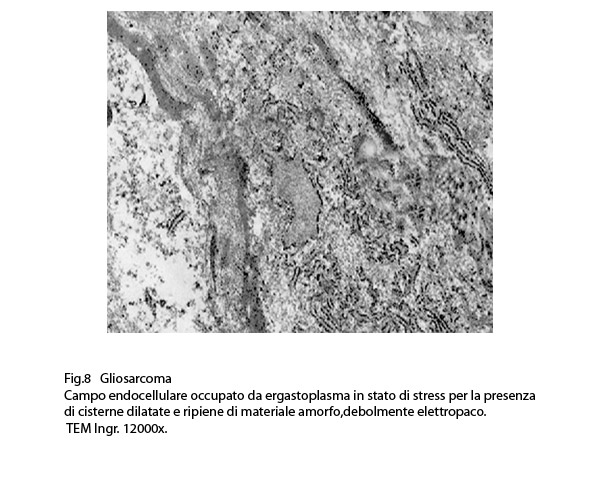

Al microscopio elettronico l’ergastoplasma in stato di stress appare con cisterne dilatate e ricolme di materiale amorfo, debolmente elettropaco.

Anche nelle cellule dei gliosarcomi quì rivisitati, si repertano disfunzioni ergastoplasmatiche; infatti si evidenziano tratti della rete ergastoplasmatiche con cisterne dilatate e ricolme di materiale amorfo, debolmente elettropaco. In un minor numero di cellule questa disfunzione si appalesa sotto forma di fasci iperdensi di sub strutture ergastoplasmatiche variamente orientate,spesso con cisterne ectasiche e occupanti una ampia area del citoplasma.

Fig.8  Fig.9

Fig.9  Fig.10